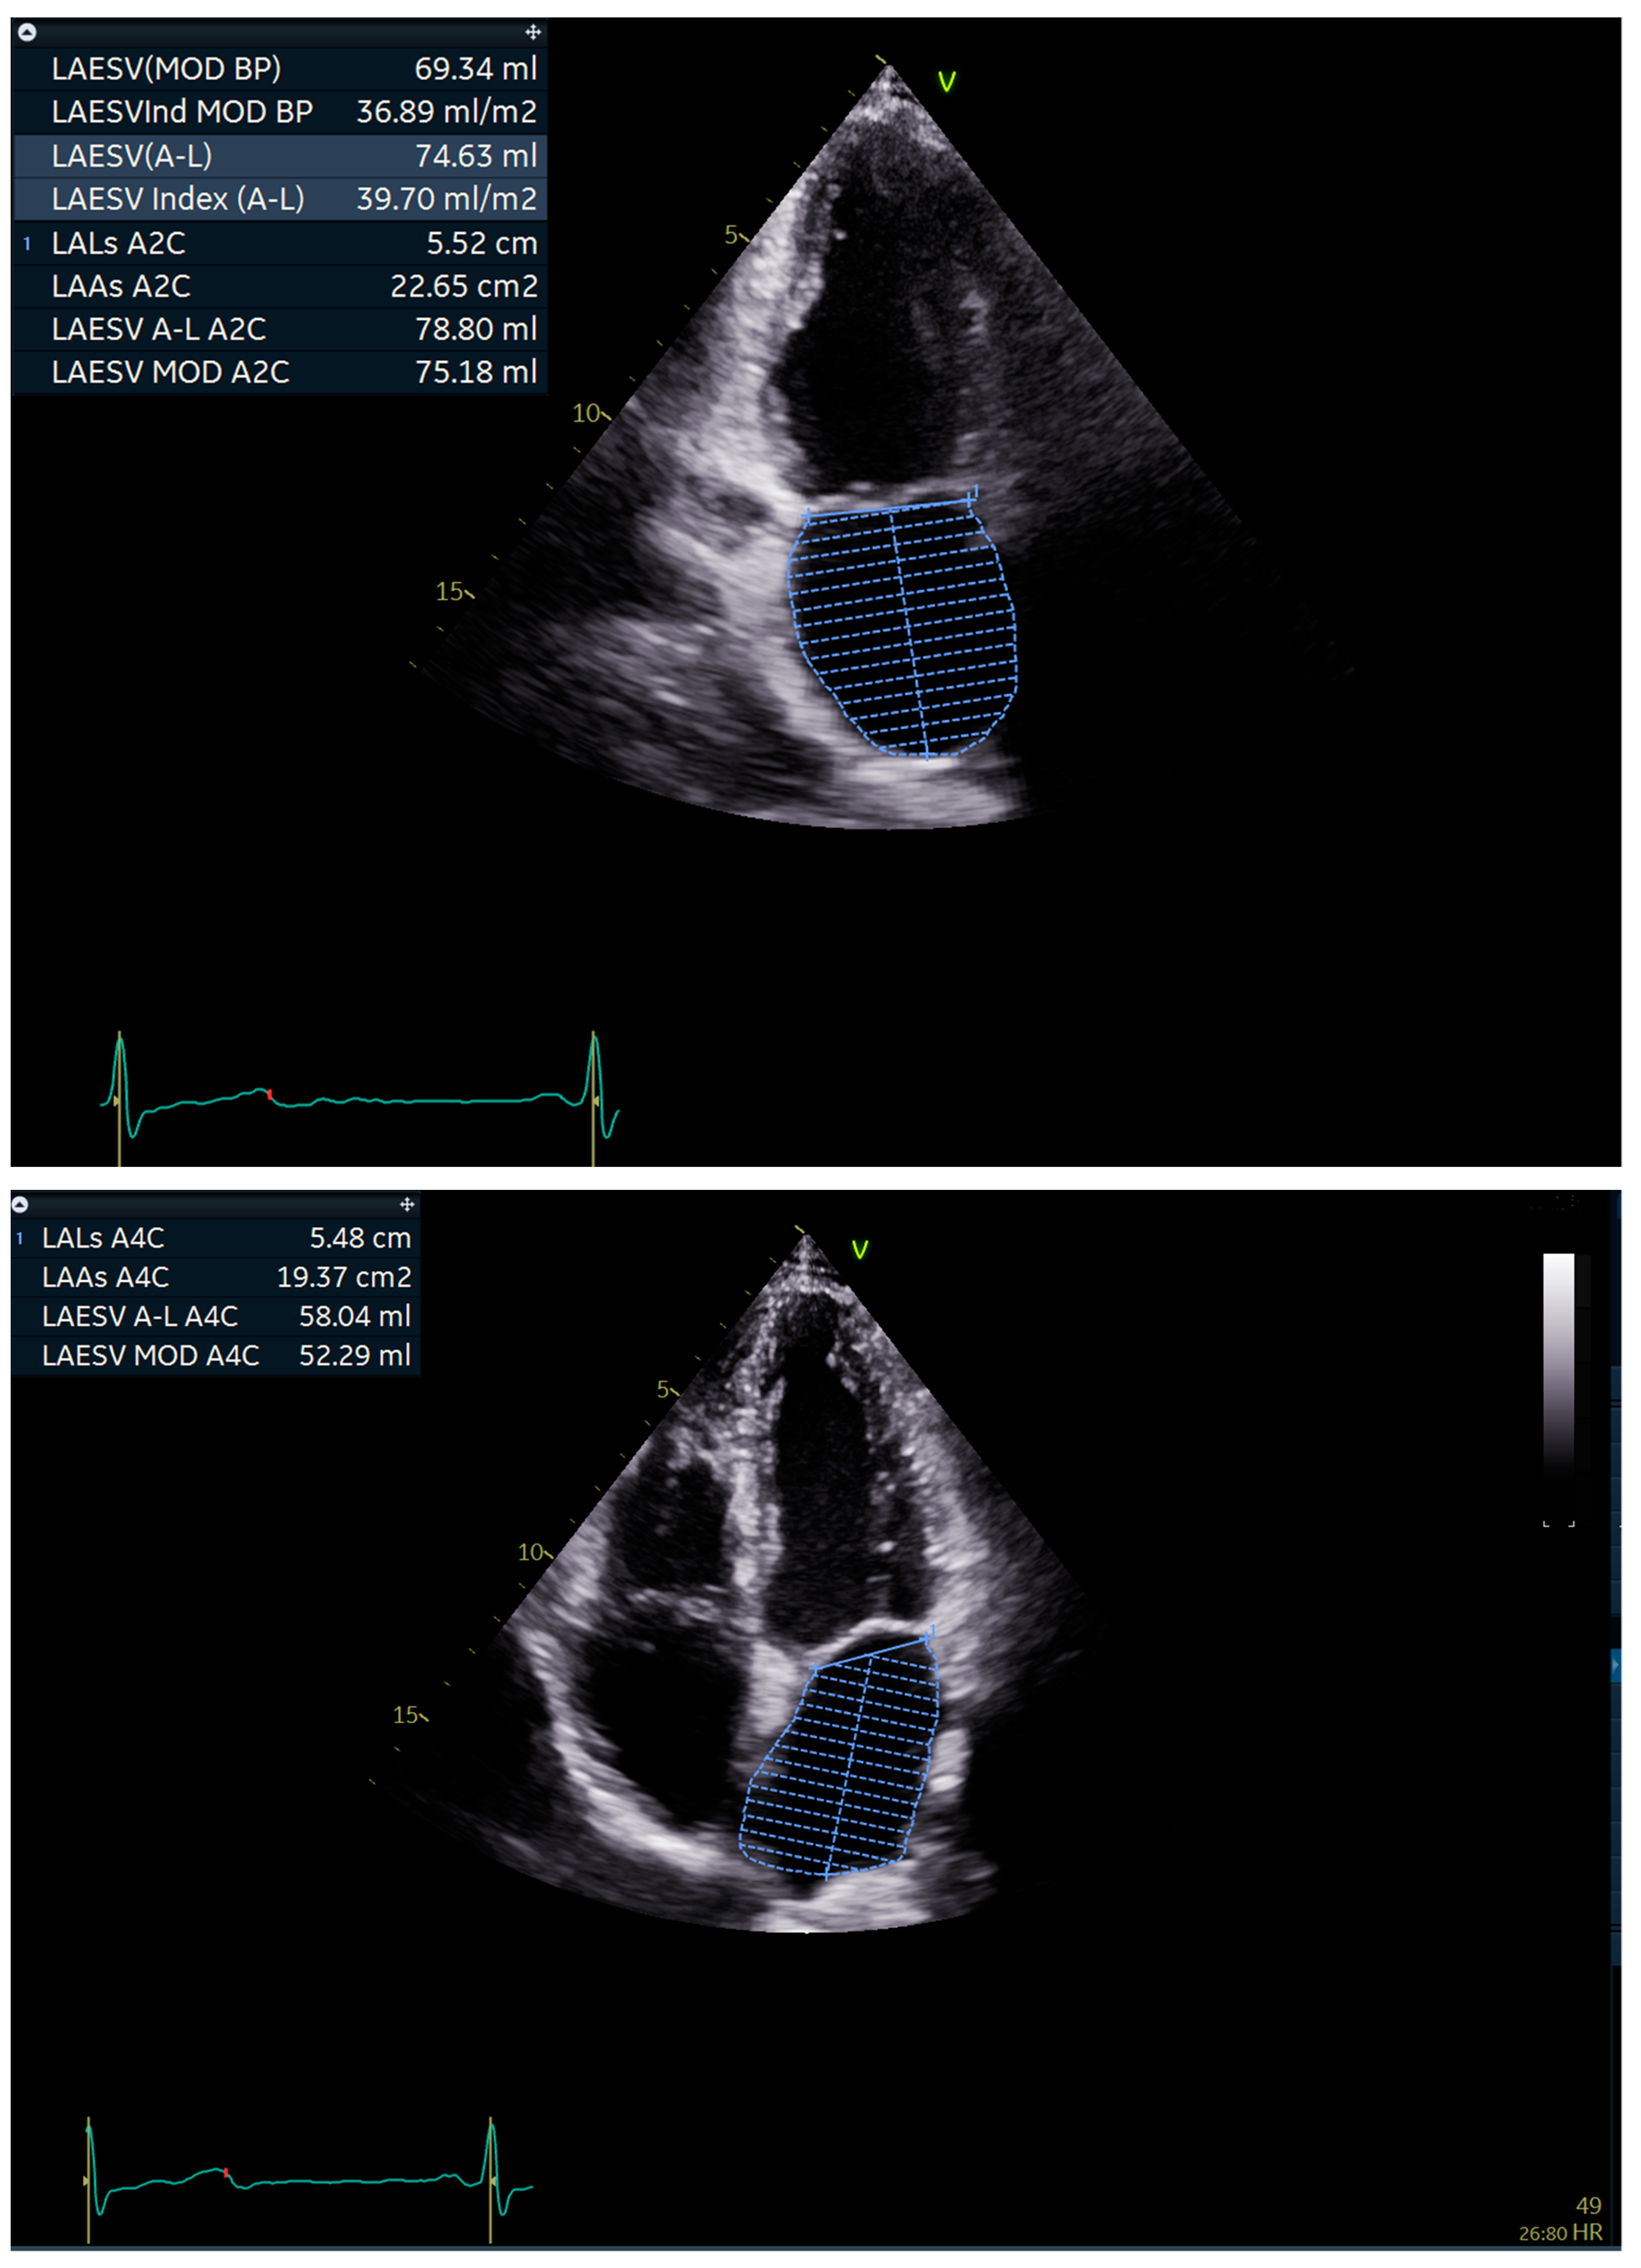

2.2. Echocardiography